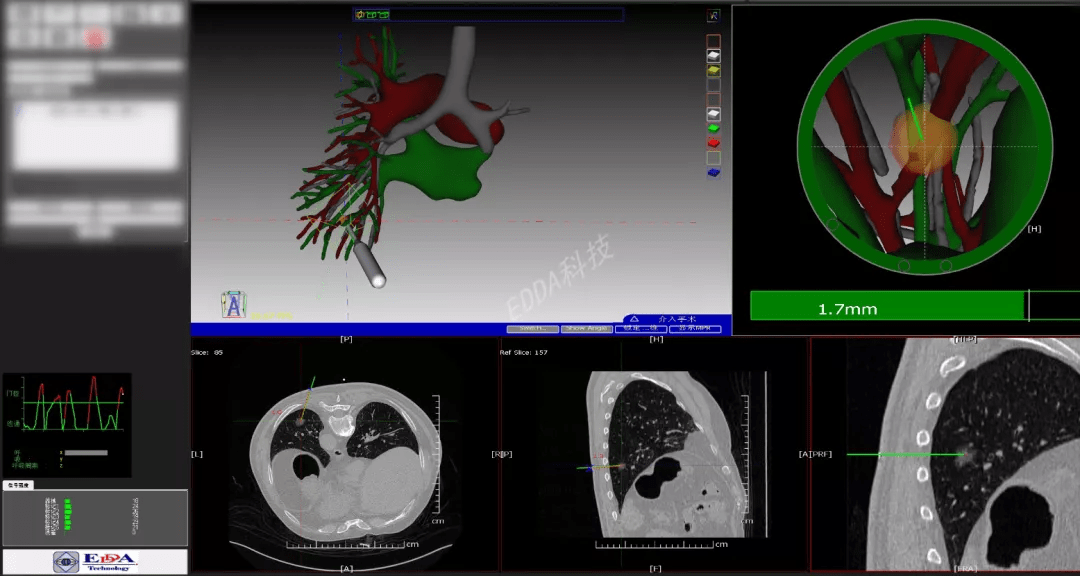

案例四:IQQA®-Guide引导下左肺下叶结节穿刺活检+等离子消融术

术者:胸外科王猛医生

病例简介:男,75岁。患者于入院前9月余单位体检发现左肺下叶结节。建议定期复查,未予治疗,随后近期复查胸部CT示上述结节与之前相仿,大小约1.7cm,右肺中叶结节5mm较前相仿。初步诊断:1.左肺下叶结节 2.冠心病 3.高血压病2级极高危组 4.陈旧性脑梗死。手术团队采用IQQA®-Guide穿刺手术导航设备进行精准定位后,成功快速实施穿刺活检手术,并实施等离子消融治疗。

上图:IQQA术前eOrganMap全量化三维重建、肿瘤精准定位

上图:医生使用IQQA®-Guide术中导航,穿刺一次,一针到位

上图:IQQA®-Guide引导下目标路径、距离、角度等全程量化动态更新